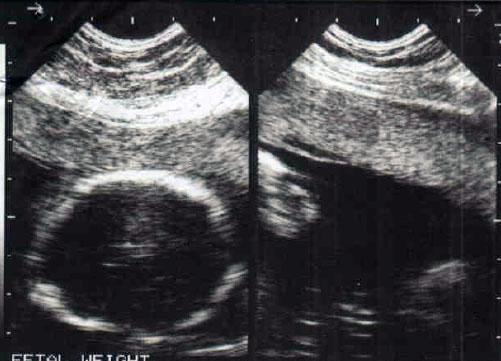

I am expecting a baby first time, below is my ultrasound images.

Please predict the gender of my baby. The ultra sound was done at 18th week.

Attachment 3128